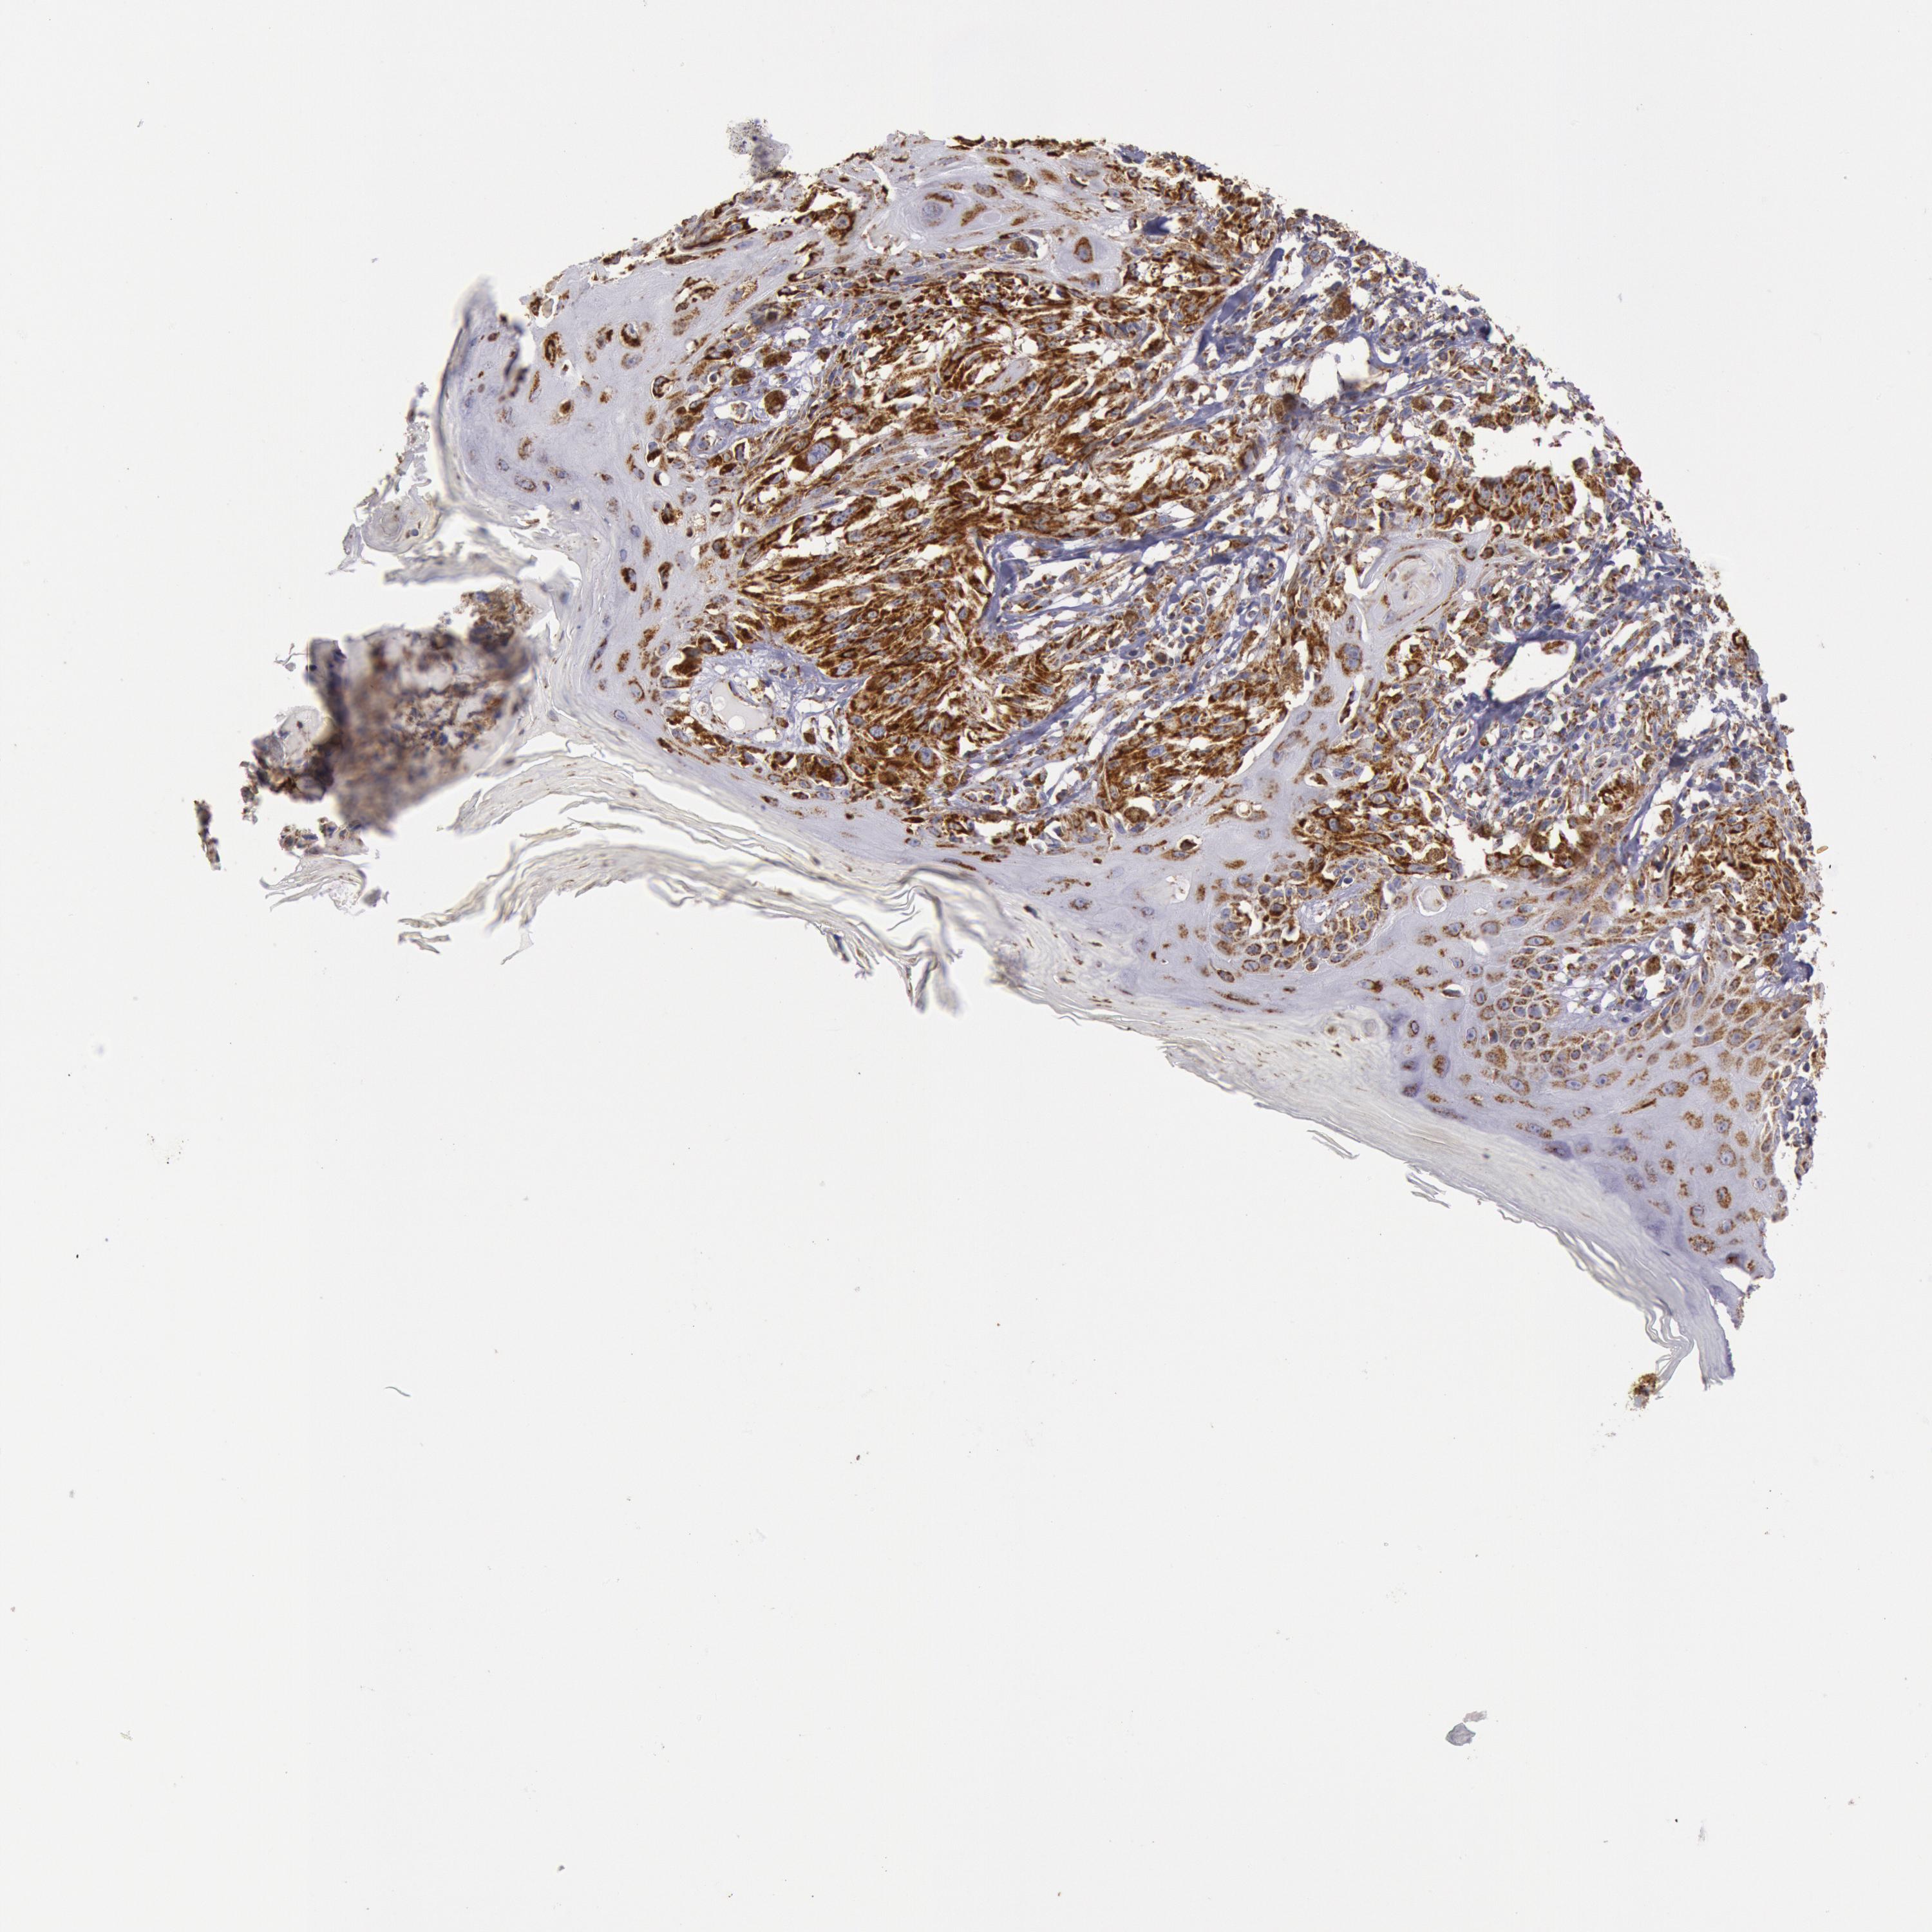

MELANOMA - Protein expressioni

A mouse-over function shows sample information and annotation data. Click on an image to view it in a full screen mode. Samples can be filtered based on level of antibody staining by selecting one or several of the following categories: high, medium, low and not detected. The assay and annotation is described here.

Note that samples used for immunohistochemistry by the Human Protein Atlas do not correspond to samples in the TCGA dataset.

Antibody stainingi

Antibody staining in the annotated cell types in the current human tissue is reported as not detected, low, medium, or high, based on conventional immunohistochemistry profiling in selected tissues. This score is based on the combination of the staining intensity and fraction of stained cells.

Each image is clickable and will lead to virtual microscopy that enables deeper exploration of all samples and also displays staining intensity scores, fraction scores and subcellular localization as well as patient and tissue information for each sample.

Antibody HPA001247

Staining

High

Medium

Low

Not detected

Intensity

Strong

Moderate

Weak

Negative

Quantity

>75%

75%-25%

<25%

None

Location

Nuclear

Cytoplasmic/membranous

Cytoplasmic/membranous,nuclear

Malignant melanoma, NOS